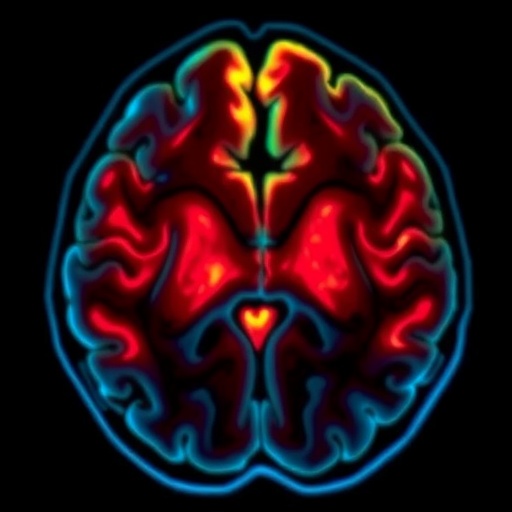

Recent research has unearthed alarming insights into the neurotoxic effects of cisplatin, a chemotherapy drug widely used in cancer treatments. This study, led by Altunkaya and colleagues, sheds light on how cisplatin can inflict damage on the hippocampus—a critical region of the brain associated with memory and learning. The findings point toward a dose-dependent mechanism of injury, indicating that as the dosage of cisplatin increases, so does the risk of significant neurotoxicity.

Altunkaya’s research employs rigorous methodologies to analyze the hippocampal tissue of subjects administered cisplatin. The study intricately examines the cellular responses that manifest in the face of increasing drug concentrations. Notably, the data unveil significant alterations in neuronal integrity, synaptic structures, and neuroinflammatory responses, starkly illustrating the risks presented by this common chemotherapeutic agent.

Moreover, the findings foster a deeper understanding of the biochemical and molecular underpinnings associated with cisplatin-induced neurotoxicity. With evidence surfacing that links heightened levels of oxidative stress and inflammation to cognitive decline, the study posits critical questions regarding patient quality of life post-treatment. As such, there is an urgent need for neuromonitoring of cancer patients undergoing chemotherapy to preemptively address the cognitive impairments that might arise.